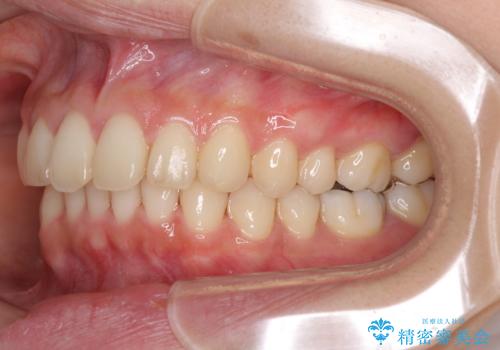

インビザラインによるディープバイトの改善

- 口元の前突感と深い咬み合わせ(ディープバイト)を気にして来院された患者様です。

インビザラインによる上下歯列の遠心移動(後方移動)と、それに伴う近心傾斜(前方傾斜)の改善により、口元の突出感とディープバイトを改善することとしました。

前歯のデコボコを最も気にしていましたが、咬み合わせが深く歯ぎしりが自由にできない点を指摘すると、常に食いしばってしまうことも悩みであることが分かりました。

咬合状態が大きく変化したため、治療後半では咬み合わせの位置が定まらなくなりました。上下の前歯に後戻り防止用のワイヤーを装着し、奥歯の咬合をフリーにしたことで1ヶ月ほどで咬み合わせが定まりました。